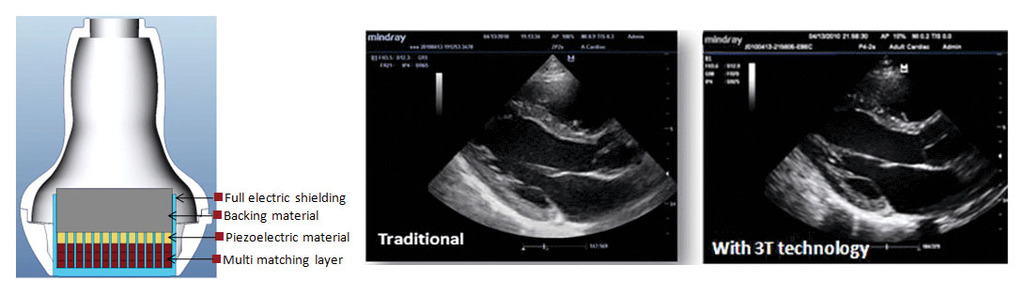

Датчики на основе технологии 3T

Датчики созданы на основе технологии, запатентованной компанией Mindray, и обеспечивают увеличение пропускной способности изображения и эффективности передачи сигнала.

Данная технология обеспечивает повышение чувствительности, увеличение пропускной способности, а также улучшение соотношения сигнал/шум

- Технология total-cut обеспечивает снижение уровня переходных помех, улучшает направленность, а также увеличивает латеральное разрешение

- Терморегулирование улучшает качество передачи акустического сигнала